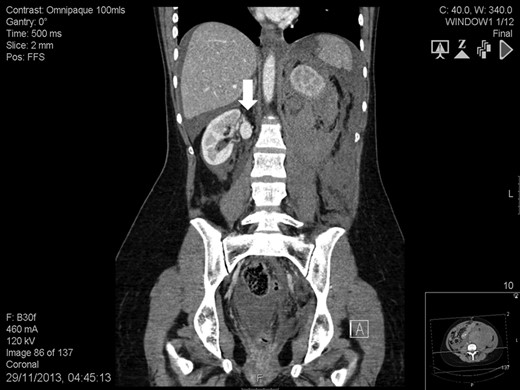

A 41-year-old woman, 21-week pregnant, presented to the Emergency Department with left-flank pain, hypotension (100/60 mmHg) and tachycardia (95 bpm). Blood tests were: haemoglobin 7.3 g/dL, leukocytosis 23.4 cell × 109/L, lactate 3.6 mmol/L, base excess −8.4 mol/L and serum creatinine 82 mmol/L. Abdominal ultrasound was normal but foetal monitoring demonstrated a drop in heart rate suggestive for impending demise. Placental abruption was suspected and following resuscitation she was brought to theatre. We found a large left-sided retroperitoneal haematoma and a non-viable foetus. Exploration also revealed a ruptured left RAA and a contralateral RAA. At this point, it was felt a percutaneous approach would have been more appropriate. Contrast-enhanced computed tomography showed a massive retroperitoneal haematoma, a ruptured left RAA (Fig. 1), and an intact right-sided RAA measuring 2.2 cm (Fig. 2). Under selective angiography, the aneurysm was embolized and the bleeding controlled [3]. Recovery was rapid but a DMSA scan performed 2 weeks later, demonstrated reduced function in the treated kidney (37%). The risk of rupture of the right RAA was deemed significant and a plan for repair was made. The lesion was saccular, wide-necked and located at the artery bifurcation thus preventing endovascular treatment. We opted for hand-assisted retroperitoneoscopic nephrectomy, ex-vivo repair and autotransplant.

Abdomen contrast-enhanced computed tomography scan: massive retroperitoneal haematoma (white arrow) with active bleeding from a ruptured 2-cm left renal artery aneurysm (black arrow).